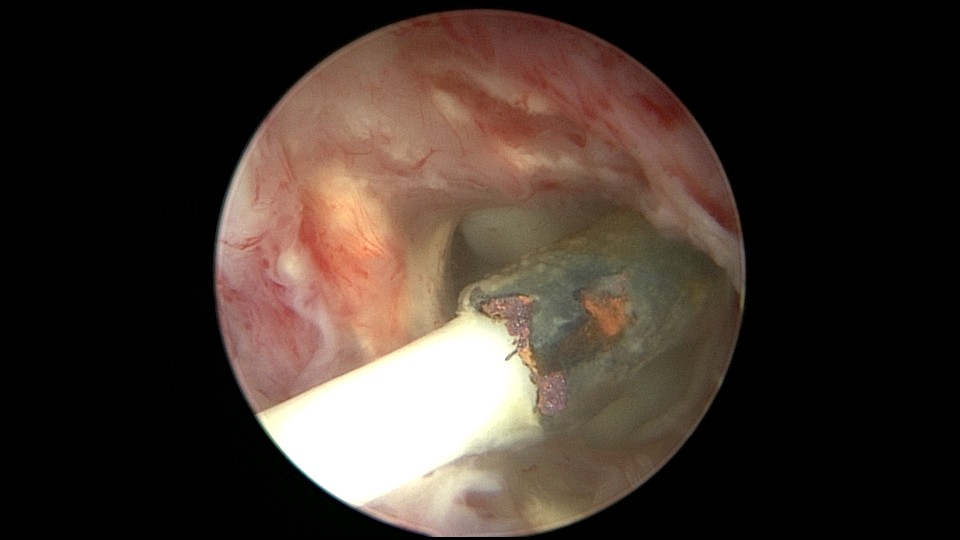

患者56岁,G3P1,顺产1次。安环20+年,绝经10年,下腹坠胀不适1周,B超提示子宫后位,宫内无回声区2.4cm×1.5cm。宫颈外口见节育环尾丝,环纵臂卡在宫颈管内,宫腔镜难以进入宫腔,取环后看到宫腔粘稠白色脓液,宫腔左侧前后壁粘连,膨宫液冲洗脓液,宫腔无其他异常。